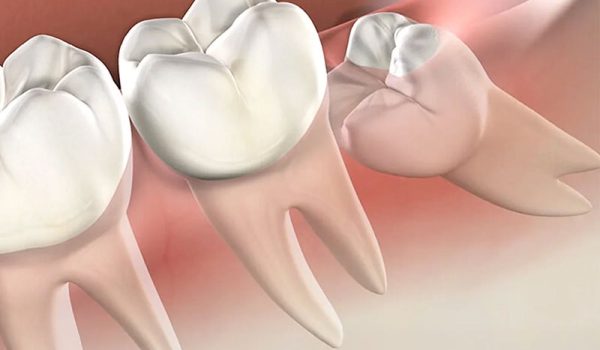

دندان عقل یا “Third Molar” سومین دندان آسیاب در هر ربع از فک بالا و پایین است که معمولاً بین سنین ۱۷ تا ۲۵ سالگی رویش میکند. از نظر تکاملی، این دندانها زمانی کاربرد داشتند که انسانها غذاهای سفتتری مصرف میکردند و سایش بیشتری روی دندانها اتفاق میافتاد.

با تغییر سبک زندگی و کوچکتر شدن فکها، دیگر جایی برای دندان عقل در دهان بسیاری از افراد وجود ندارد. به همین دلیل دندان عقل نهفته، نیمهنهفته یا دارای زاویه رشد اشتباه، باعث درد، عفونت و بههمریختگی نظم دندانها میشود.

در بیش از ۸۰٪ موارد، دندان عقل به علت نبود فضای کافی، بهصورت نهفته یا کج رشد میکند و مشکلات زیر را ایجاد میکند:

- فشار به دندانهای مجاور

- التهاب لثه و عفونتهای مکرر

- پوسیدگی دندان عقل و دندان کناری

- کیست یا تومور اطراف دندان نهفته